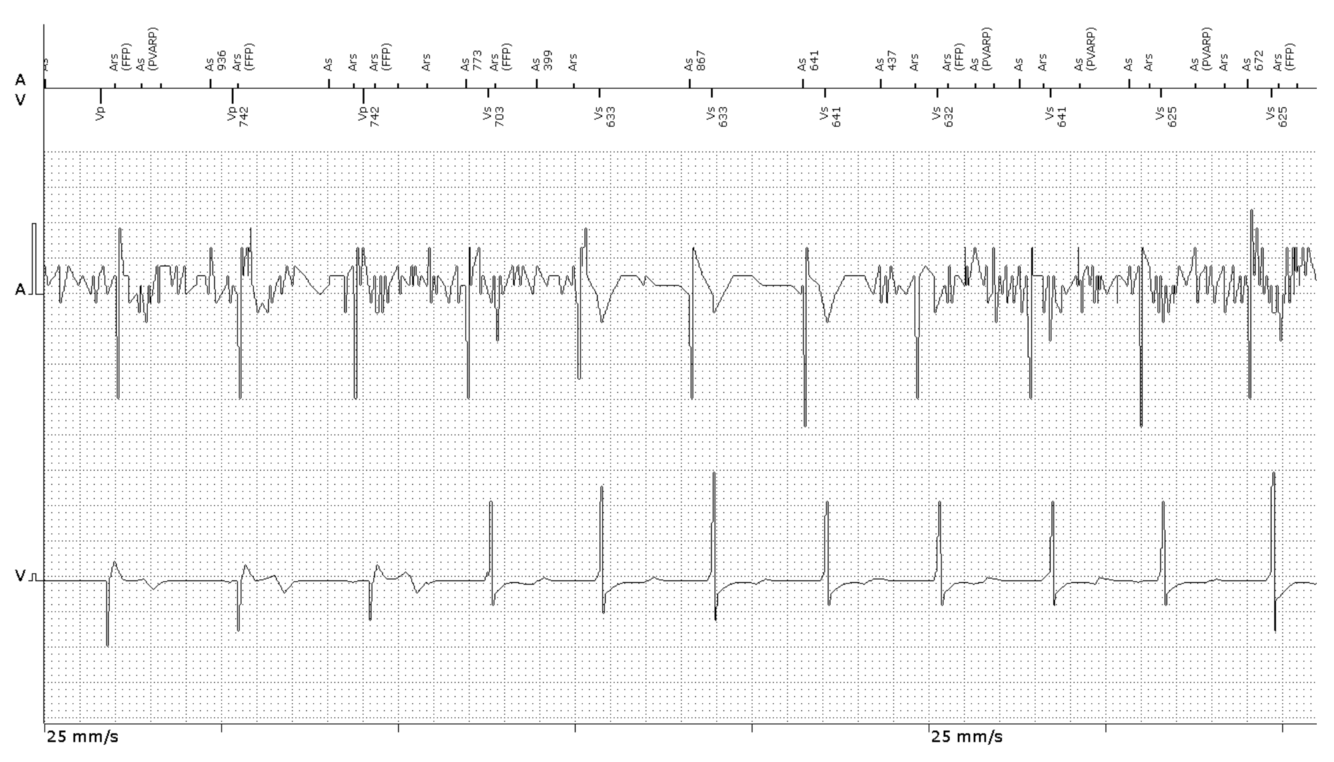

In clinic you are presented with this atrial lead noise. List two ways to program around it.

You see dropped p-waves on this IEGM, what would you adjust to ensure appropriate sensing?

Increase atrial sensitivity (lower number).

The amplitude of the dropped p-waves is significantly less than the preceding sensed p-waves. Thus making the atrial channel more sensitive is likely to correct the problem.